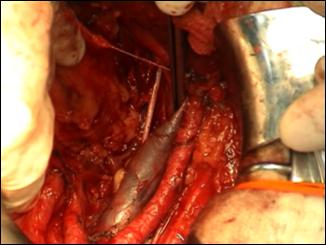

a. b.

Figura

18. a,b. Disectia uretrei

si spatularea acesteia. a)

schema anatomica; b)

aspect intraoperator.